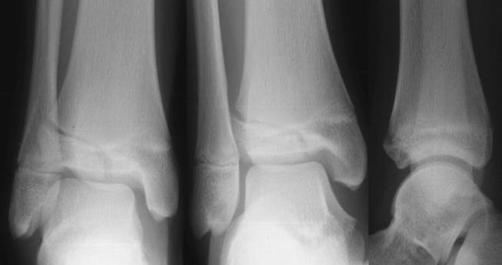

Fractura intertrohanteriana multifragmentara Luxatie de patela